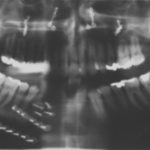

Vor der Einleitung der Analgesie, die noch ein Mitagieren des Patienten ermöglichte, wurde der Patient an das Monitoring angeschlossen. Die eingehende Untersuchung stellte ein im Unterkieferknochen links steckendes Geschoss dar, welches in Haut und Muskulatur einen ca. 5 cm großen Defekt verursacht hatte. Mehrere kleine Einsprengungen verteilt über die linke Gesichtshälfte von der Schläfe bis zum Hals (Bild 2) waren für die Primärversorgung zunächst ohne Relevanz. Nach Sicherung der Vitalfunktionen und Analgesie, wurden zwei Röntgenaufnahmen (PSA und HWS) angefertigt, die übereinstimmend eine Fraktur der Mandibula ausschlossen (Bild 1).

In der anschließenden problemlosen Intubationsnarkose erfolgte die Entfernung des Projektils durch die Eintrittswunde (Bild 3 und 4). Auftretende Blutungen konnten durch Elektrokoagulation gestillt werden. Des weiteren wurde ein Debridement der Wunde durchgeführt und die Wunde mit Kochsalz-Lösung gespült. Es erfolgte ein Wundverschluss in mehreren Schichten mit eingelegter Drainage (Bild 5).